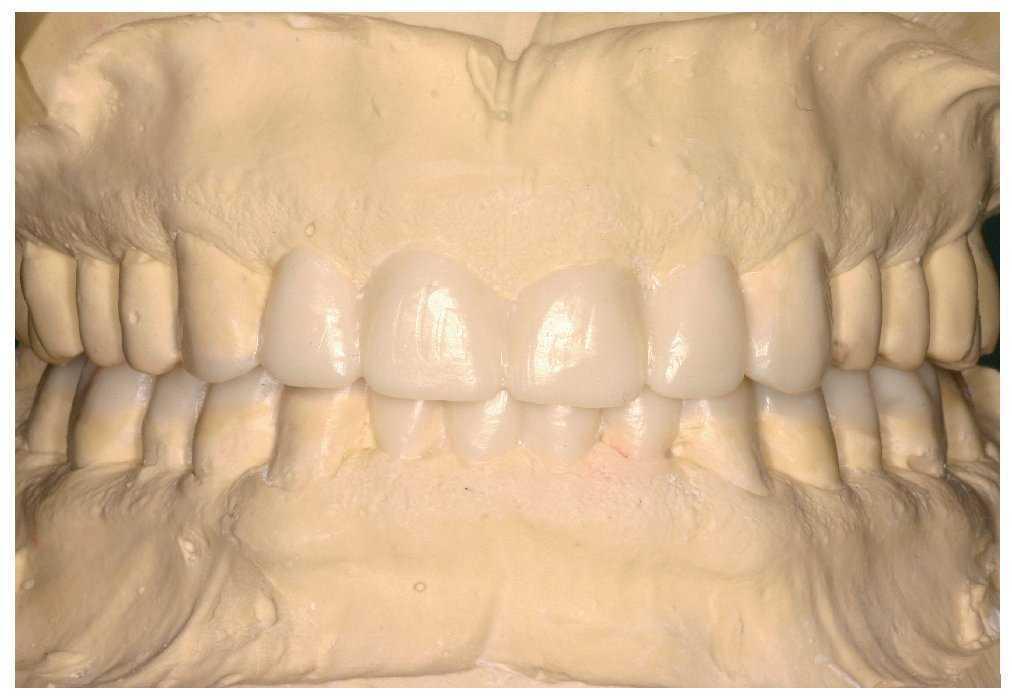

Después del registro de mordida provisional se confeccionó un encerado diagnóstico (fig. 5). El aumento de la dimensión vertical previsto era de 5,5 mm (medido en los incisivos centrales superiores). En el maxilar el encerado se limitó a los dientes anteriores, mientras que en la mandíbula fue necesario reconstruir la arcada completa (fig. 6). El diente 48, clínicamente asintomático durante muchos años, debía ser conservado por deseo expreso del paciente y no se tuvo en cuenta en la planificación de las restauraciones indirectas. El contacto con el antagonista se debía crear con ayuda de una reconstrucción directa con composite.

Figura 5. Encerado tras la apertura de la dimensión vertical.

El encerado de la reconstrucción prevista confeccionado durante la fase de planificación sirvió de modelo para las restauraciones. Se escanearon los modelos duplicados de ambas arcadas (Organical Scan D 640). Se determinó en el articulador la relación oclusal del encerado con una silicona de registro de mordida (Platinum 85, Zhermack, Badia Polesine, Italia) y también fue escaneada.

Se utilizó el software disponible (DentalDesigner, 3Shape) para sincronizar los conjuntos de datos de la situación después de la preparación, del encerado y del registro. Después de esta fase de trabajo se corrigió la forma inicial de las restauraciones con un instrumento de modelado virtual. El resultado fueron conjuntos de datos para el fresado de las coronas de recubrimiento parcial 34 a 37 y 44 a 47 (fig. 13) con superficies masticatorias anatómicas cuyo modelo había sido el primer encerado de la fase de planificación. Durante el diseño se procuró dotar de unas dimensiones suficientes a las cofias de las coronas unitarias 13 a 23 y a la estructura con pónticos del puente del sector anteroinferior (fig. 14). Por esa razón las cofias se confeccionaron con una pared de al menos 0,6 mm de grosor y los conectores con una sección mínima de 9 mm2 y una altura mínima de 3 mm respectivamente.